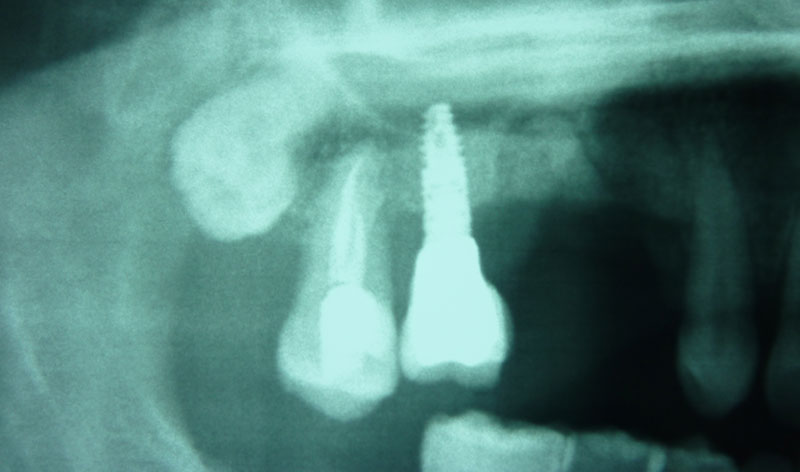

Procedimiento: se realiza una incisión en la encía, se aborda el hueso maxilar superior realizando una pequeña apertura en el margen externo del maxilar, y se introduce un cemento formado por el propio hueso y sangre del paciente, y un material óseo conductor, que proporciona una serie de condiciones básicas para la formación de hueso.

Una vez realizada la intervención, en algunos casos se pueden colocar los implantes a la misma vez y en otros, es necesario esperar seis meses para que el material óseo forme un hueso con buena calidad que asegure el éxito de los implantes.